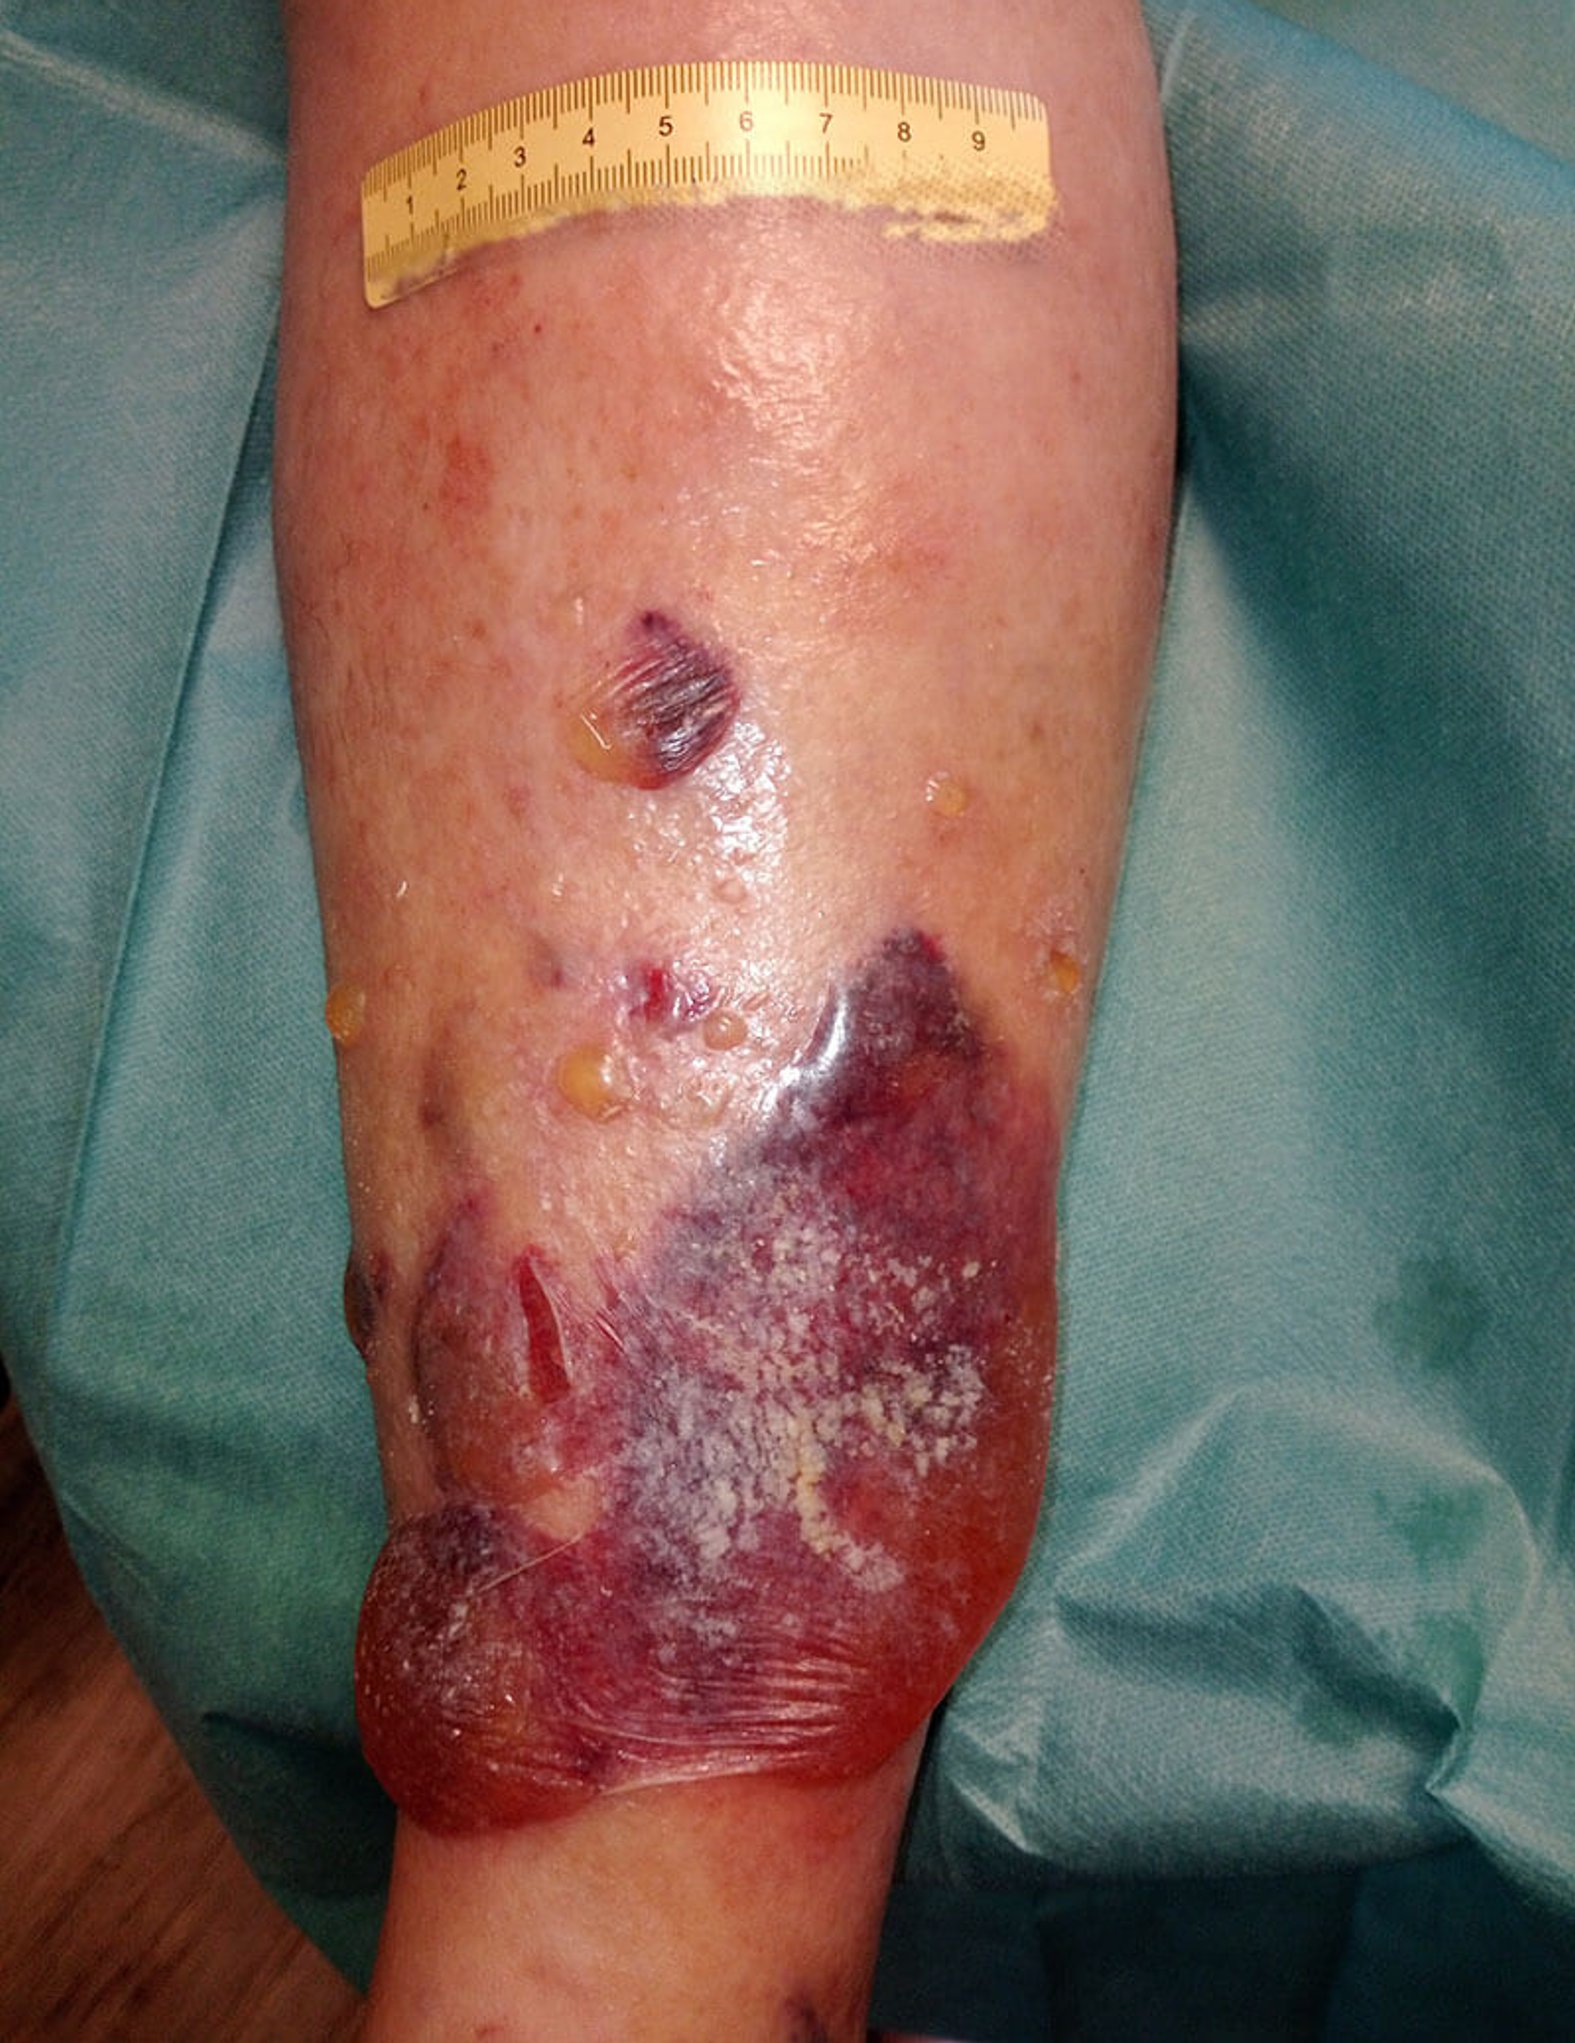

Nach 4 Tagen ist die Wunde deutlich trockener, die Ödeme haben sich insgesamt verringert (Bild 3). An den Wundrändern ist weiterhin sich lösende Oberhaut erkennbar, die beim Verbandwechsel entfernt wird. Die Versorgung erfolgt nun mit einem PU-Schaum und der Fixierung wie oben beschrieben. Der Verband soll nun 6 Tage verbleiben.